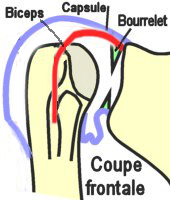

ÉPAULE - Articulation SCAPULO-HUMERALE

Généralités

Généralités

Articulation proximale du bras qui relie le membre supérieur au tronc.

C'est une énarthrose typique à 3 ddl

formée par l'union de la cavité glénoïdale de la scapula

(old. omoplate) et de la tête

humérale. Entre les deux, il existe un bourrelet glénoïdal (ou

labrum).

Surfaces Articulaires

- La tête de l'humérus forme une saillie à

l'extrémité supéro-interne de l'os et représente le 1/3 d'une sphère

recouverte de cartilage (rayon : env. 30 mm). Elle regarde en HT, en

DD et en ARR.

- La cavité glénoïdale de la scapula est ovale

et quasi plane, elle regarde en HT, en AV et en DH. Au dessus et en

dessous de cette cavité, on observe les tubercules sus et sous

glénoïdiens (respectivement lieu de naissance du tendon de la longue

portion du biceps et de la longue portion du triceps).

- Le bourrelet glénoïdal est un

fibro-cartilage qui s'insère sur le pourtour de la cavité glénoïdale

de la scapula qu'il agrandit et creuse. Triangulaire à la coupe, il

forme un anneau plus large et plus épais en BAS qu'en HT. Il est

constitué de fibres propres circulaires et de fibres de renforcement

en provenance des tendons de la longue portion du biceps et du triceps

brachial.